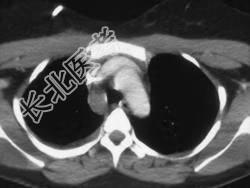

- 单项选择题男,33岁, 车祸后十余天,请结合影像学检查, 选出最可能的诊断 ( )

A、纵隔畸胎瘤

B、胸内甲状腺肿

C、胸腺瘤

D、淋巴瘤

E、纵隔血肿